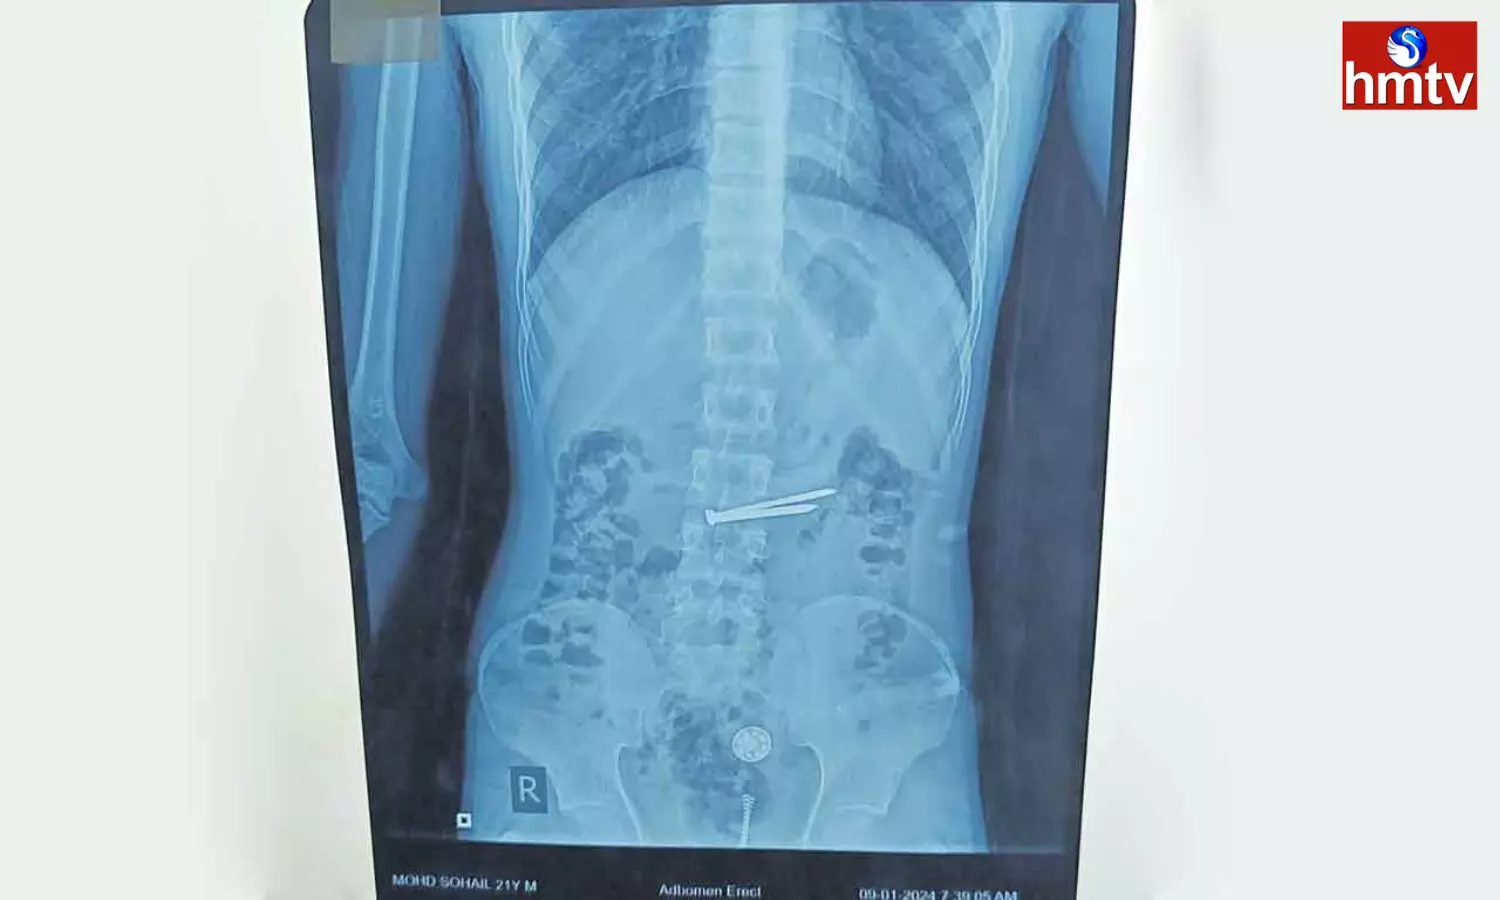

Prisoners Stomach: చంచల్‌గూడ జైలులో ఖైదీగా ఉన్న 21 ఏళ్ల మహమ్మద్‌ సొహైల్‌ కడుపులో ఉన్న 8 రకాల మెటల్స్‌ను ఉస్మానియా ఆస్పత్రి వైద్యులు విజయవంతంగా తొలగించి ప్రాణాలను కాపాడారు. జైలులో ఉన్న సొహైల్‌ గత కొంత కాలంగా కడుపు నొప్పితో భాధ పడుతూ ఉండటంతో జైలు అధికారులు ఉస్మానియా ఆస్పత్రికికి చికిత్స నిమిత్తం తరలించారు. జనరల్‌ సర్జరీ విభాగం యూనిట్‌-7 డాక్టర్‌ రోగిని పర్యవేక్షించి మెడికల్‌ గ్యాస్ట్రో ఎంట్రాలజీ విభాగానికి రిఫర్‌ చేశారు. గ్యాస్ట్రో ఎంట్రాలజీ విభాగం హెచ్‌ఓడీ రోగికి ఎక్స్‌రే తీయించగా కడుపులో మేకులు, గోర్లు, ప్లాస్టిక్‌ వస్తువులు, మెటల్‌ ఉన్నట్లు గుర్తించారు. సుమారు గంట పాటు శ్రమించి ఎండోస్కోపి సహాయంతో వాటిని తొలగించారు. ప్రస్తుతం రోగి పూర్తిగా కోలుకొని ఆరోగ్యంగా ఉన్నట్లు వైద్యులు తెలిపారు.